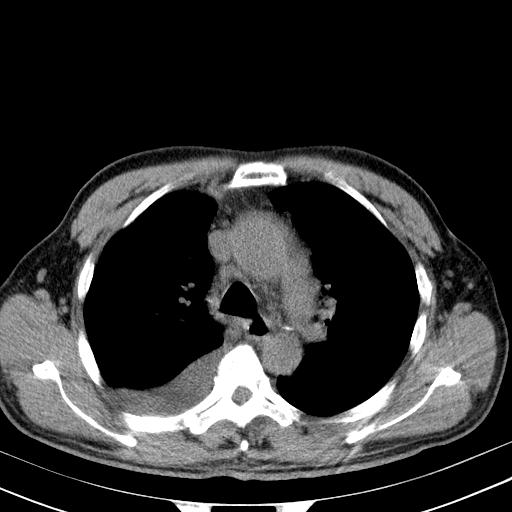

以下是引用zjzjr在2010-3-21 17:39:00的发言:[br]右下中心型肺癌并阻塞性肺炎/不张,纵膈淋巴结肿大,右侧大量胸腔积液,左侧少量胸腔积液

以下是引用zxl51642在2010-3-21 17:06:00的发言:[br]右下中心型肺癌并阻塞性肺炎/不张,纵膈淋巴结肿大,右侧大量胸腔积液,左侧少量胸腔积液,少量腹水。建议纤维支气管镜进一步检查。